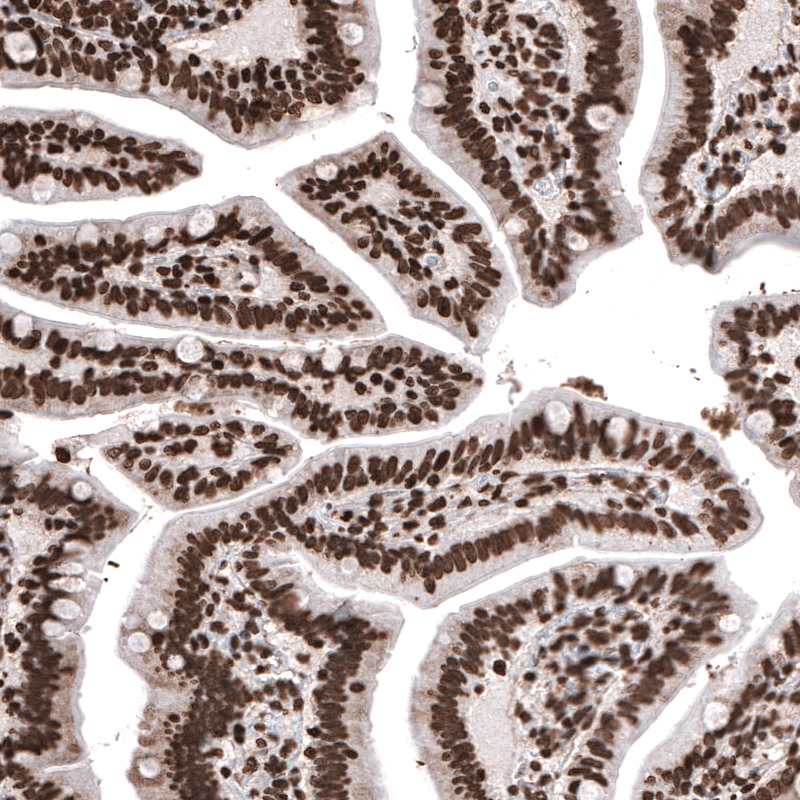

Immunohistochemical staining of human prostate shows strong nuclear immunoreactivity in glandular and smooth muscle cells.